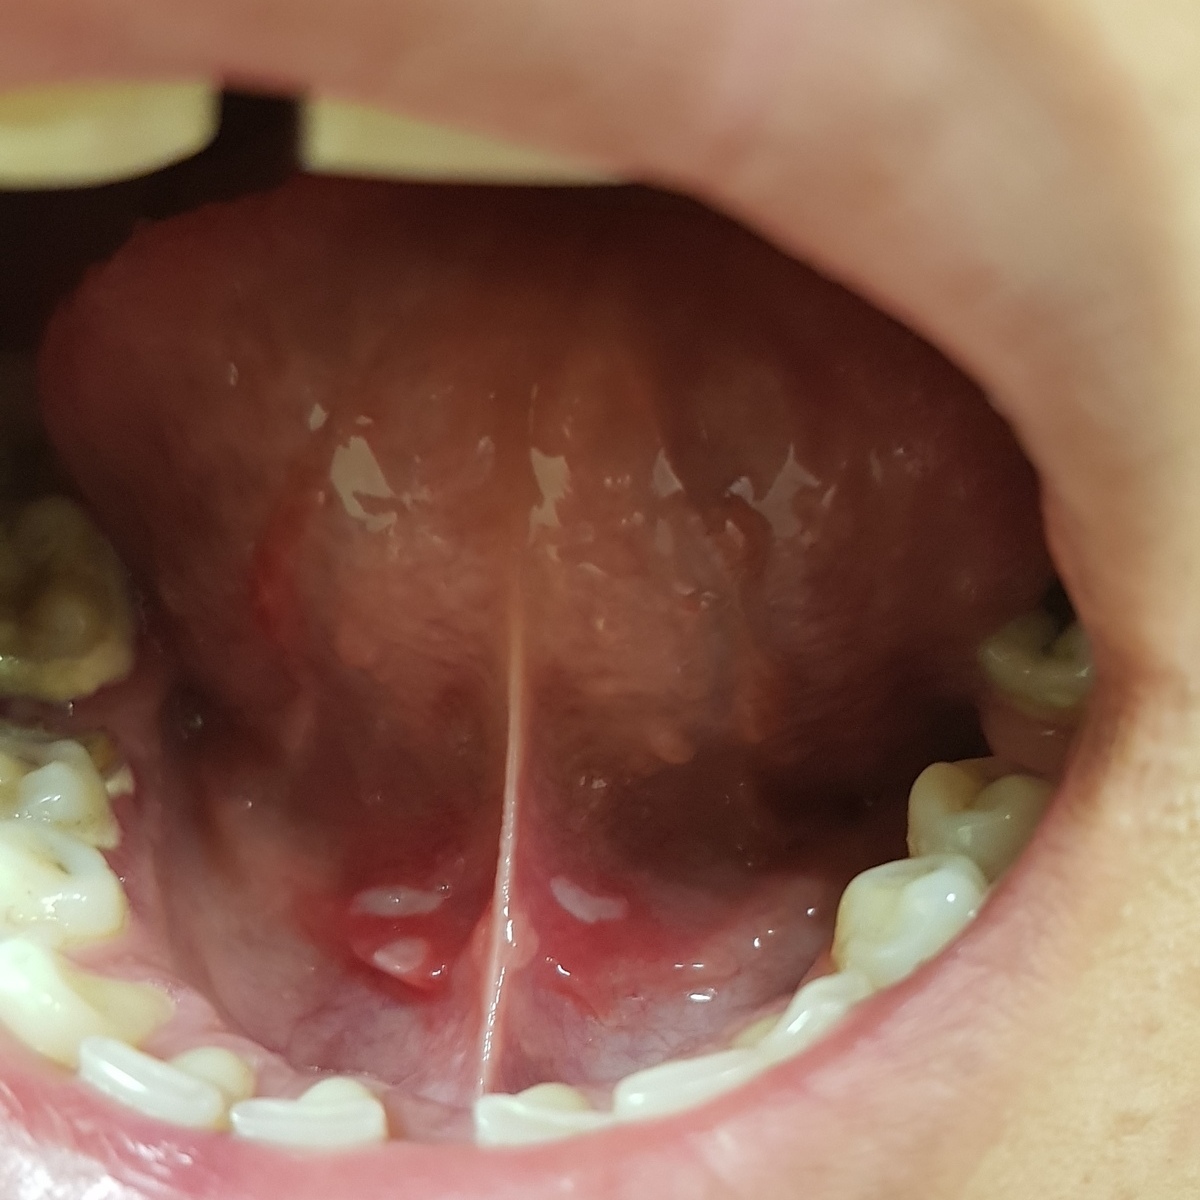

Поскольку уреаплазма поражает преимущественно мочеполовые пути, передаваться она может в первую очередь во время незащищенных половых контактов.

При этом опасность представляют не только классические сексуальные связи.

Но и их более экзотические варианты, если пара пренебрегает презервативом сознательно.